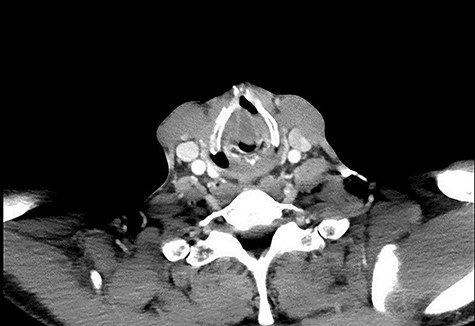

Axial CT showing obstruction at the level of the vocal cords. Media: video showing the laryngocoele.

On examination, he was tachypnoeic, with a respiratory rate of 32 and oxygen saturations of 92% on room air. Although he was afebrile and haemodynamically stable, he was visibly exhausted, with accessory muscle use and stridulous breathing. There were no palpable swellings in the patient’s neck. Flexible nasoendoscopy showed a large submucosal swelling arising from the right vestibular fold, causing intermittent airway obstruction (Video) (Fig. 2). Laboratory markers were within normal range. Computed tomography of neck showed a well-defined, peripherally enhancing collection in right paraglottic space, extending from level of hyoid bone into the right laryngeal ventricle, with significant airway compromise at the level of the vocal cords (Figs 3 and 4).